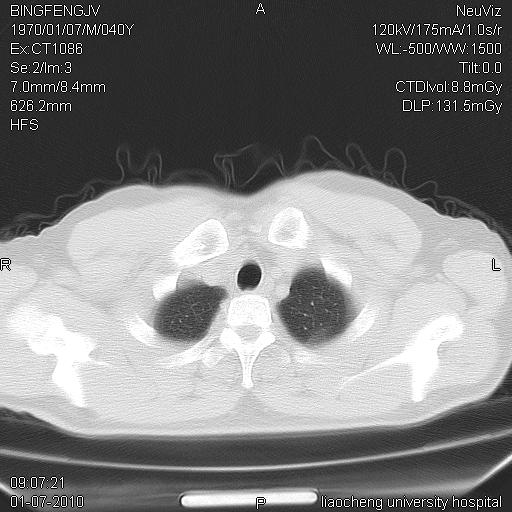

标题: CT23764B:男 40 肺部CT [打印本页]

标题: CT23764B:男 40 肺部CT

治疗2周后

炎症性病灶,继发性改变。

考虑左肺上叶近胸膜下炎症并肺气囊形成。

炎症,大部吸收。